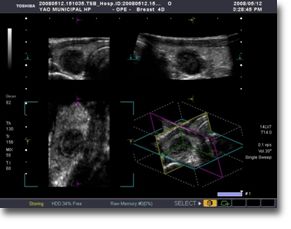

超音波検査室

超音波検査は人間の可聴範囲を超える音波を利用し、体内を画像化して評価します。体に害のない音波を利用しているため、安心して受診していただけます。

現在、超音波検査室では医師と共に5 名のソノグラファーで検査を行っています。(超音波検査士5 名、血管診療技師2名)超音波診断装置は4 台で稼動しています。